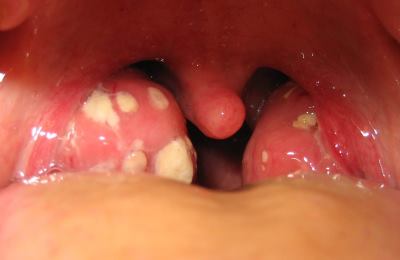

Как выглядит горло при фолликулярной ангине?

Изменения миндалин. Основной признак фолликулярной ангины – нагноение фолликулов небных миндалин. Воспаляясь, они отекают, увеличиваются в объеме и становятся красными. На их поверхности появляются небольшие, величиной до 3-4 мм, беловато-желтые островки — это и есть нагноившиеся фолликулы.